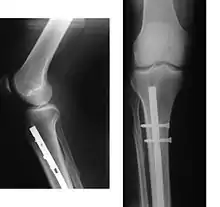

Рентгеновское исследование позволяет более точно установить вид перелома и положение отломков. Рентгенография — стандартный метод диагностики при подтверждении перелома. Именно наличие рентгеновского снимка повреждённого участка служит объективным подтверждением факта перелома. На снимке должны быть изображены два сустава, расположенные дистальней и проксимальней места поражения, кость должна быть изображена в двух проекциях, прямой и боковой. При соблюдении этих условий рентгеновское исследование будет адекватным и полноценным, а возможность ошибочной диагностики минимальна.[L 8]

|

На рентгенограмме изображён перелом большеберцовой кости, подвергшийся хирургическому лечению. 4 снимка в 2 проекциях. На первой паре снимков — верхняя треть голени и коленный сустав (сустав, расположенный проксимальней места перелома), на второй паре снимков — голеностопный сустав (сустав, расположенный дистальней места перелома). Большеберцовая кость фиксирована антероградно введённым в костно-мозговой канал гвоздём (UTN — unreamed tibial nail), блокированным 5 винтами. Такая конструкция позволяет фиксировать отломки и обеспечивает адекватную регенерацию. После формирования костной мозоли металлофиксатор удаляется.